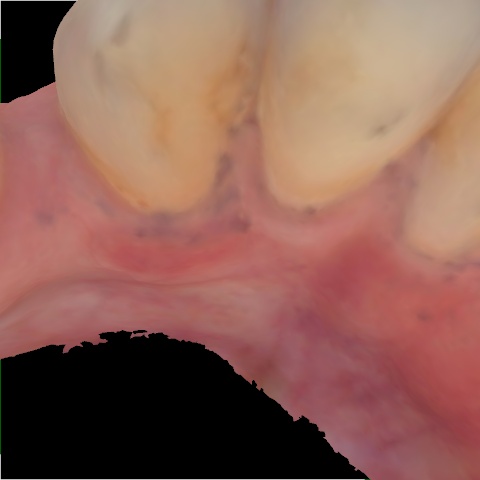

Image 66 / 400

NHD20738

Annotated as "Bad"

Original Image Rendering Image